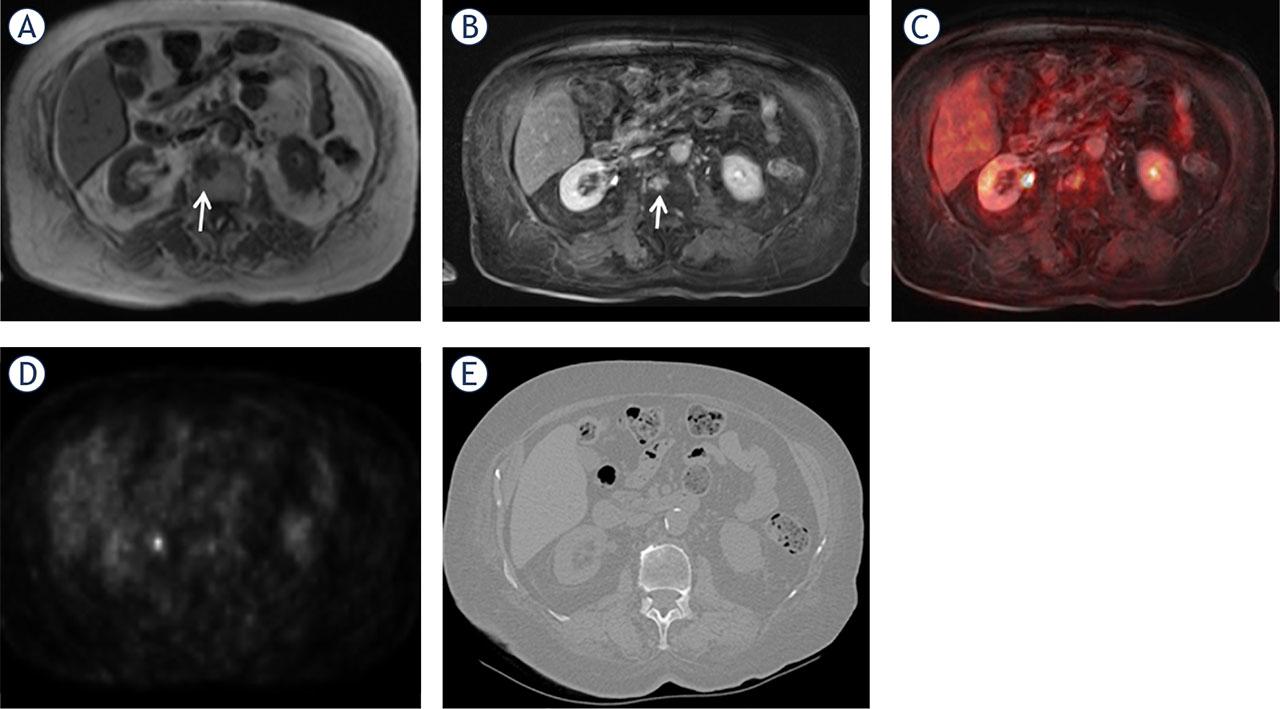

A 53-year-old woman with breast cancer. A metastasis can be observed in the L2 vertebral body (arrows) on the precontrast T1 weighted (W) image (A), contrast enhanced (CE) T1W image (B), and CE T1W VIBE-PET fused image (C). The AC PET axial image (D) does not show FDG uptake. CT yielded false-negative results (E).

AC PET = attenuation-corrected raw data positron-emission tomography; FDG = fluorodeoxyglucose; VIBE = volume-interpolated breath-hold examination